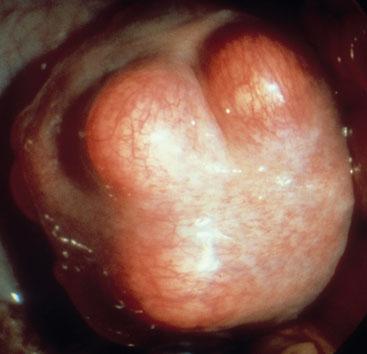

Ovarian Cancer

Ovarian cancer is the fifth most common cancer affecting women and predominantly affects women after the menopause. About 1 in 10 cases may have a genetic link. It can present with a range of symptoms including a distended abdomen which may relate to tumour growth or the development of ascites. Surprisingly, it may also cause symptoms that refer to the gastro-intestinal tract, i.e. bloating and extreme indigestion. CA125 is used as marker of ovarian cancer. However, not all tumours produce a raised test and the level may also be low in the early stages of development. Treatment will usually involve surgery and chemotherapy